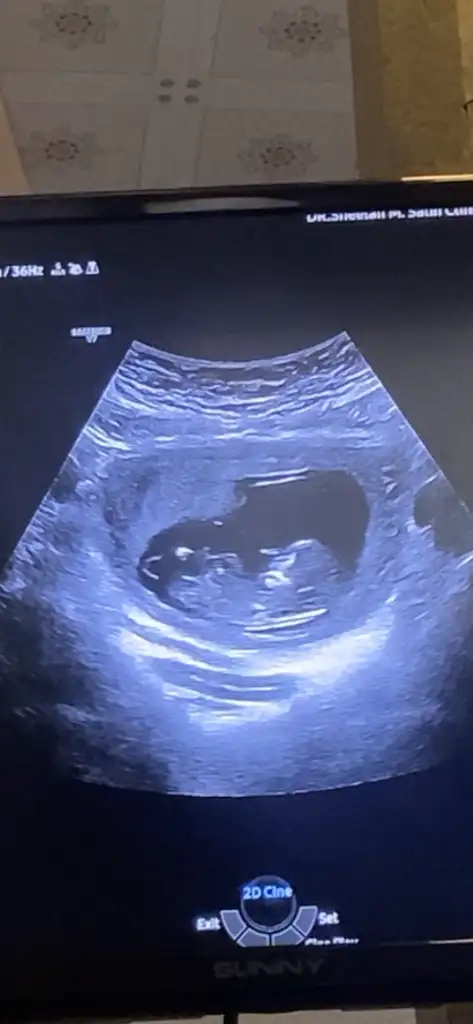

Zaten benim 13+1 belki de görünmedi daha kasigi kapatiyormus

14 haftalıklı videoda net gözüküyorda ben bunu yakalayabildim sizinkindede arada böyle bir çıkıntı gözüküyorsa erkektirAnladım sizinki de çok bariz değil galiba büyük göstermiyor kac hafta

Belkide olabilir farklı pozisyonlardan bakınca doktor belli oluyorda bu gittiğinizde netleşir ilk çocuğunuzmuZaten benim 13+1 belki de görünmedi daha kasigi kapatiyormus